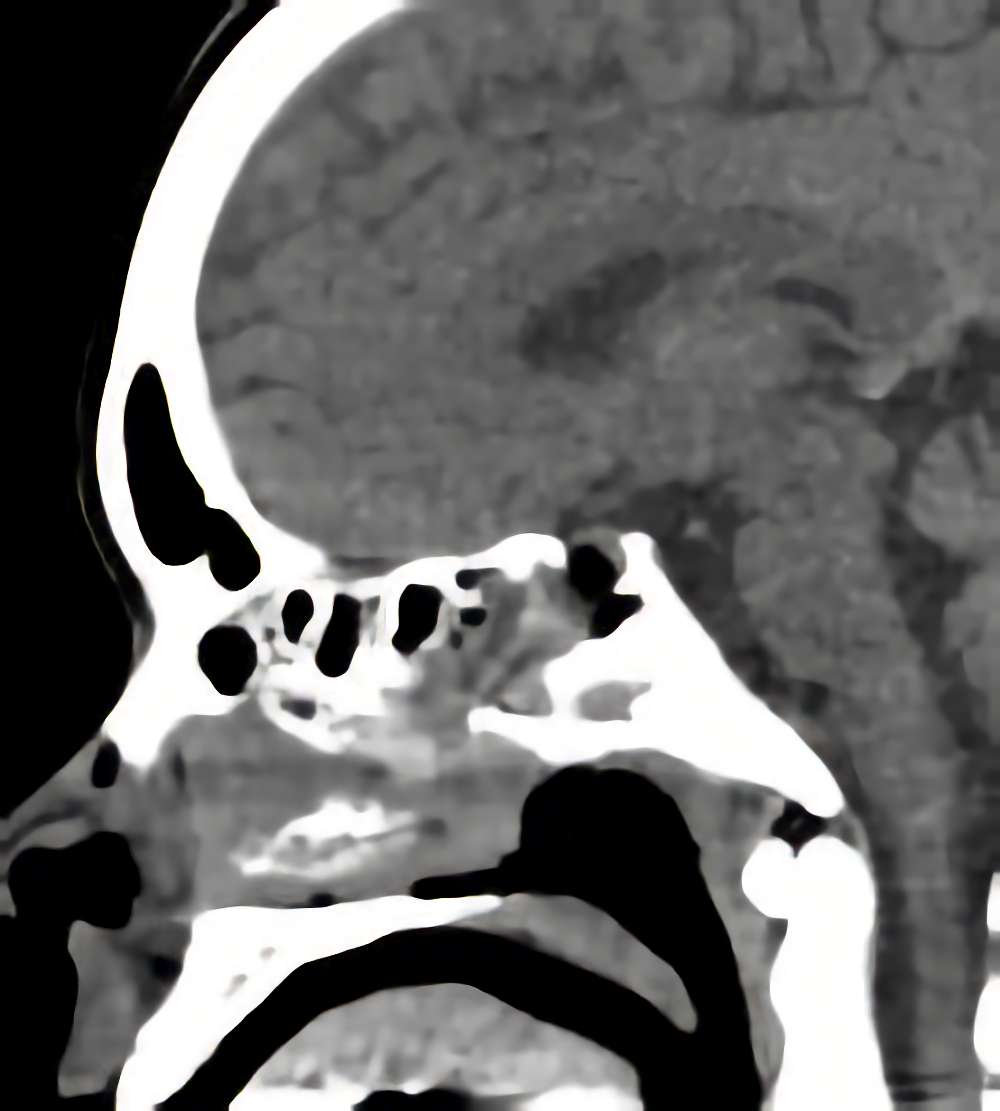

症例 '15年7月

No.

年_番号

手術年月

患者年齢

’15_96

'15年7月

30代

病名

術式

備考

下垂体腺腫

断層撮影

手術前

1

手術前2

手術後